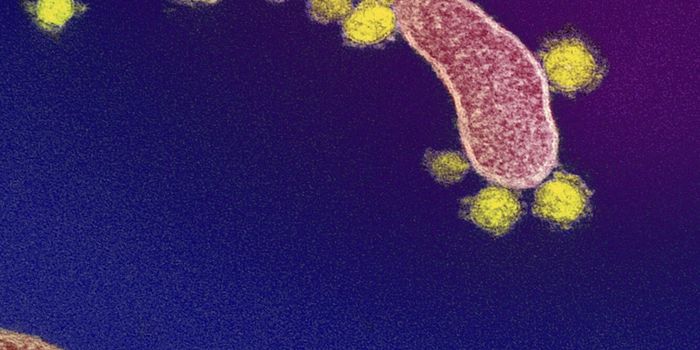

JUN 07, 2024MicrobiologySome of these antibodies could potentially neutralize coronaviruses that have not yet emerged, the study authors suggest ...